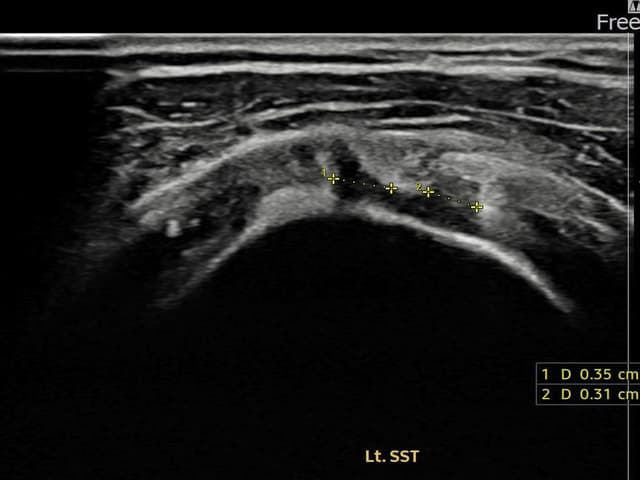

[촬영시기:22.09.02~22.11.15]

[어깨인대 축소봉합술] 좌측 어깨 통증과 팔을 올릴 때 뻐근함이 지속되어 내원하셨습니다.